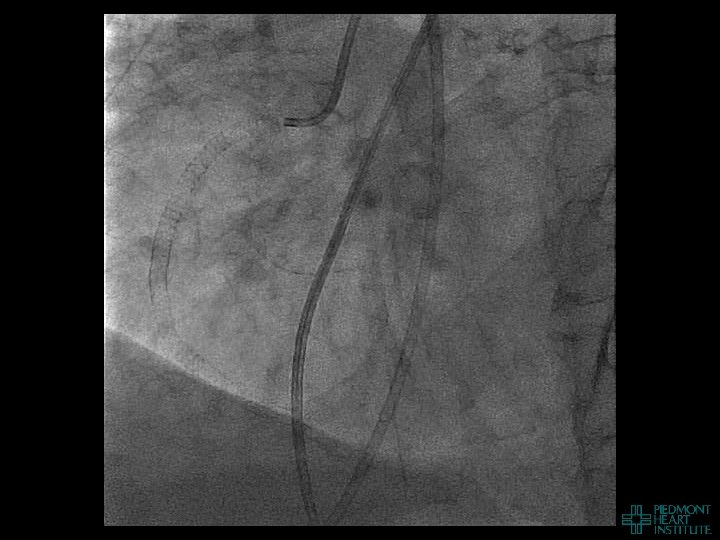

Case Example 5